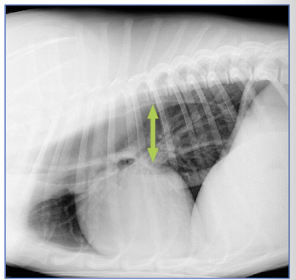

What are 2 causes of gastric dilation?

young puppies after overeating

source of distending gas (aerophagia), fluid, or food → obstruction of cardia & pylorus

What types of dogs are at risk of developing GDV?

large, deep chested breeds (Danes, St. Bernards, Irish Setters, Wolfhounds, etc)

What is the “formula” of events that leads to a GDV?

lax gastrohepatic ligament + overfeeding, postprandial exercise + other predisposing factors

The stomach rotates ________ on the __________ axis when view from the _______ surface.

clockwise

ventrodorsal

ventral

Rotation of the stomach during a GDV is about _______ degrees.

180-360

What other organs can be affected by a GDV?